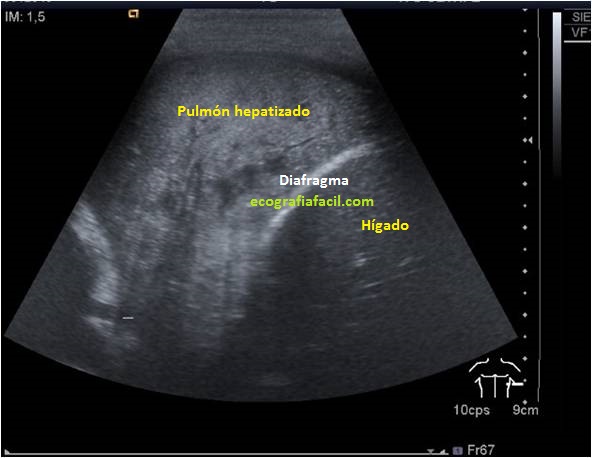

Una preciosa imagen que podemos ver habitualmente es estas patologías es el «Pulmón Hepatizado».Es una figura patológica producida por la compactación patológica del pulmón a consecuencia de un proceso infeccioso habitualmente. Tiene un aspecto muy similar al Hígado, y a veces solo podemos diferenciarlos por la separación que se produce por el Diafragma, como te enseño en la imagen superior.

A precious image that we can usually see is these pathologies is the «Hepatized Lung». It is a pathological figure produced by the pathological compaction of the lung as a result of an infectious process usually. It looks very similar to the Liver, and sometimes we can only differentiate them by the separation produced by the Diaphragm, as I show you in the image above.